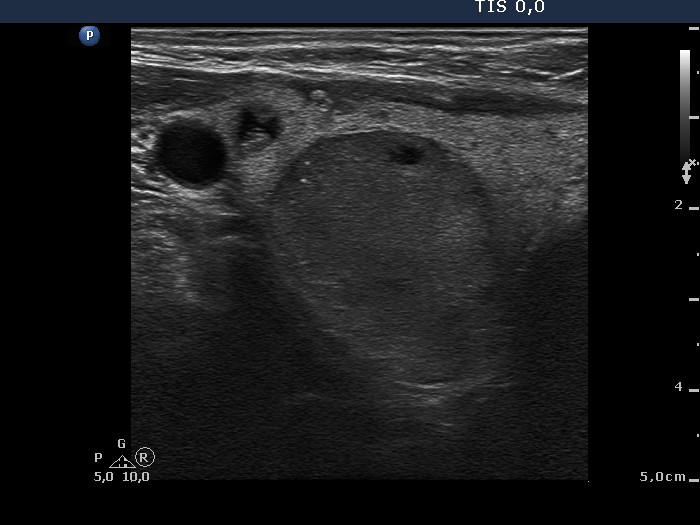

The larger lesion has a solitary bright figure which shape stands for a comet-tail artifact.

There are pale lines and granules within the nodule - these figures correspond to a connective tissue. The three granules are probably also presentations of a connective tissue.